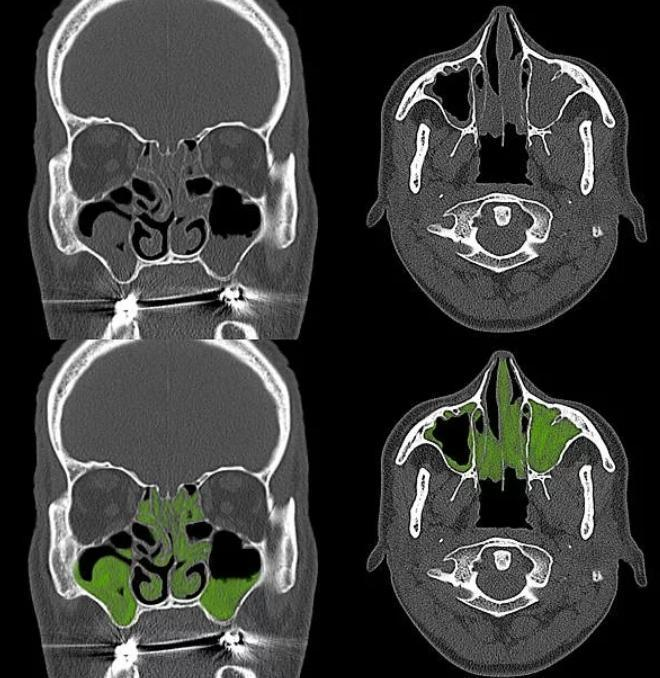

Обычно врач начинает со сбора подробного анамнеза и физического осмотра. Затем может предложить провести серию тестов, таких как анализ крови, анализы мокроты, рентген или компьютерную томографию грудной клетки и околоносовых пазух, дыхательные тесты (спирометрию), тесты на визуализацию реснитчатого эпителия, консультацию генетика.

Рисунок: КТ пазух носа двустороннее поражение пазух (что характерно при ПЦД)